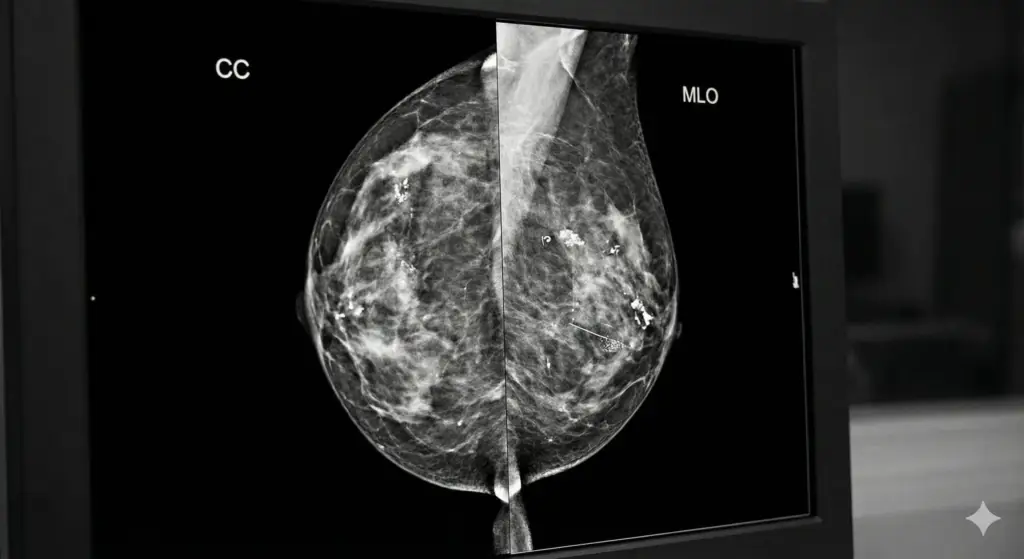

We provide accurate ultrasound, OB/GYN care, and diagnostic imaging in a friendly, professional, and patient-centered environment.